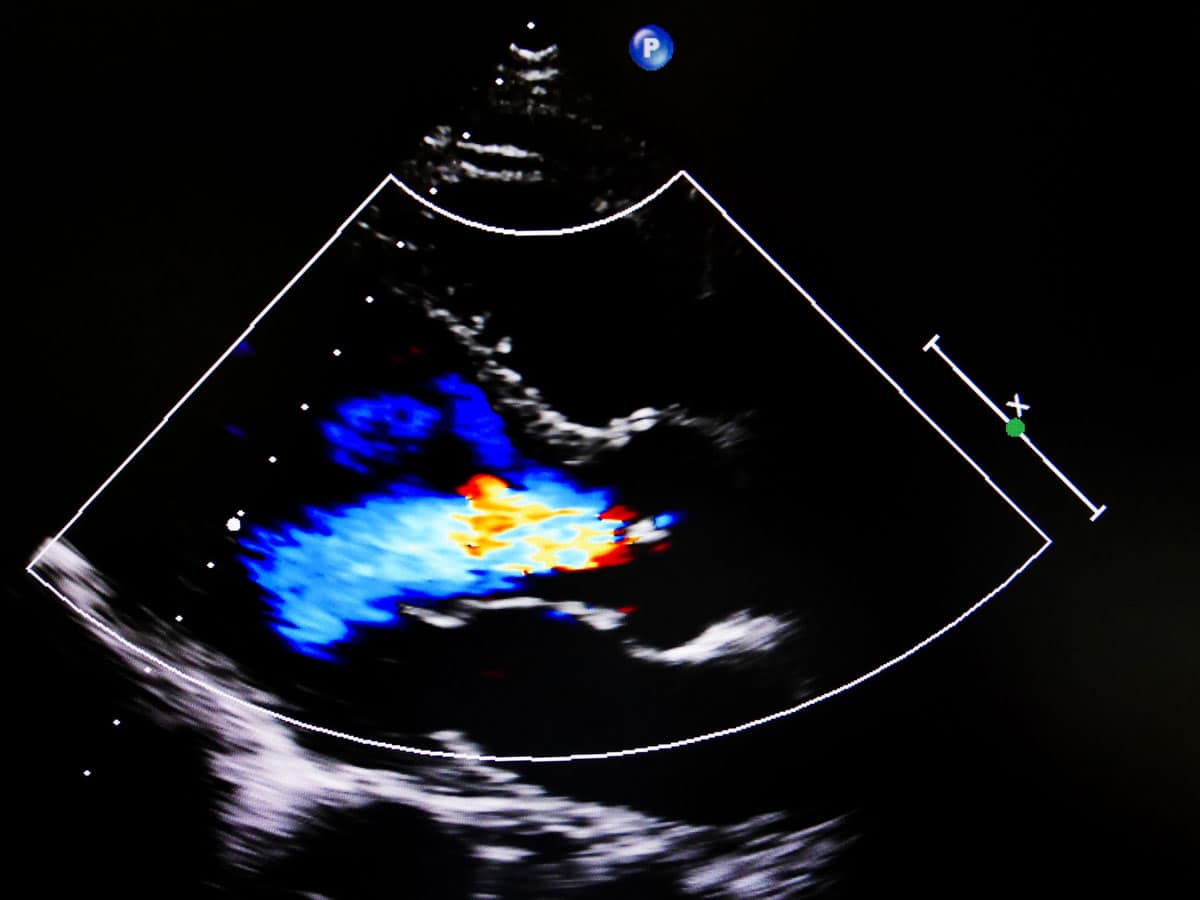

Ecocardiograma Doppler en Color

El ecocardiograma doppler color transtorácico es una prueba diagnóstica fundamental, no invasiva, no dolorosa y sin efectos secundarios que nos permite observar los grandes vasos y el movimiento del corazón (latidos) a tiempo real. Además aporta información acerca de sus estructuras, forma, tamaño, grosor y función. Con ella, determinamos también de forma no invasiva las presiones intracardíacas y pulmonares, la fuerza de contracción, así como el volumen que eyecta en cada latido. Podemos medir la velocidad y la presión de la sangre que pasa a través de cada una de las válvulas.

El ecocardiograma es una prueba de referencia cardiológica que permite el diagnóstico, evaluación y monitorización de:

- Alcance del daño en pacientes con infarto de miocardio.

- Válvulas cardíacas anormales y pacientes operado de las válvulas.

- Soplos cardíacos.

- Patologías en grandes vasos

- Patologías del pericardio.

- Cardiopatías congénitas y tumores.

- Fibrilación auricular.

- Hipertensión pulmonar.

Realizamos este estudio dentro de los programas básicos de prevención de muerte súbita, de forma rutinaria en pacientes con factores de riesgo cardiovascular o sospecha de enfermedad cardiaca.